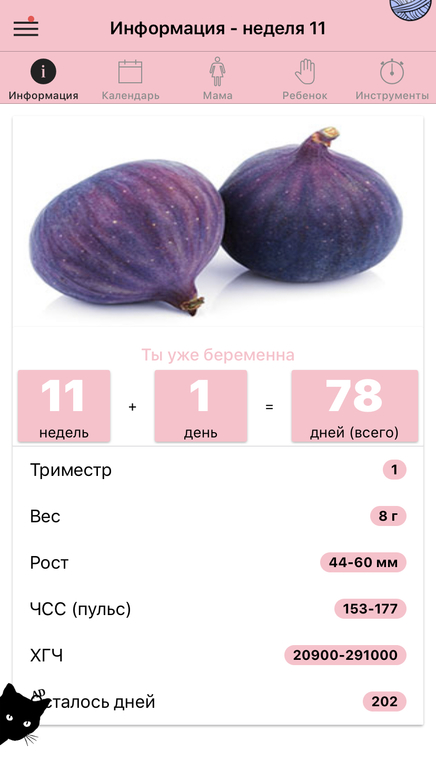

Ходили мы все же в платную клинику что бы убедится все же. Миомы подтвердились аж 2шт. Никогда их небыло, срок по узи 11 и 1. Показали малыша со всех сторон фото сделали сердечко дали послушать. Такая прелесть, я хоть чуток успокоилась. Он такой хороший малыш. Сказала ходите беременность спокойно, миомы вас не должны сейчас волновать.